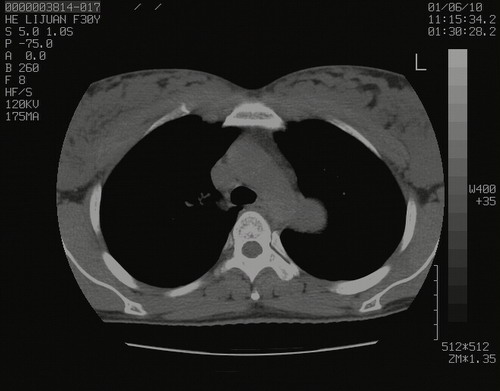

怀孕3个月时(2009-3至4月间),自述突感左侧前后胸疼痛1天,以前胸明显,随后偶感闷痛,余未见异

左肺尖脊柱旁沟肿块,境界清楚,边缘光滑,密度不均,内有多发点片状钙化,考虑良性肿瘤,骨软骨瘤或神经源性肿瘤可能,肺错构瘤不除外。

左后上纵隔见一类圆形肿块影,外侧边界清,密度不均匀,内可见点状钙化影,增强呈不均匀强化,考虑神经源性肿瘤可能。期待病理结果。